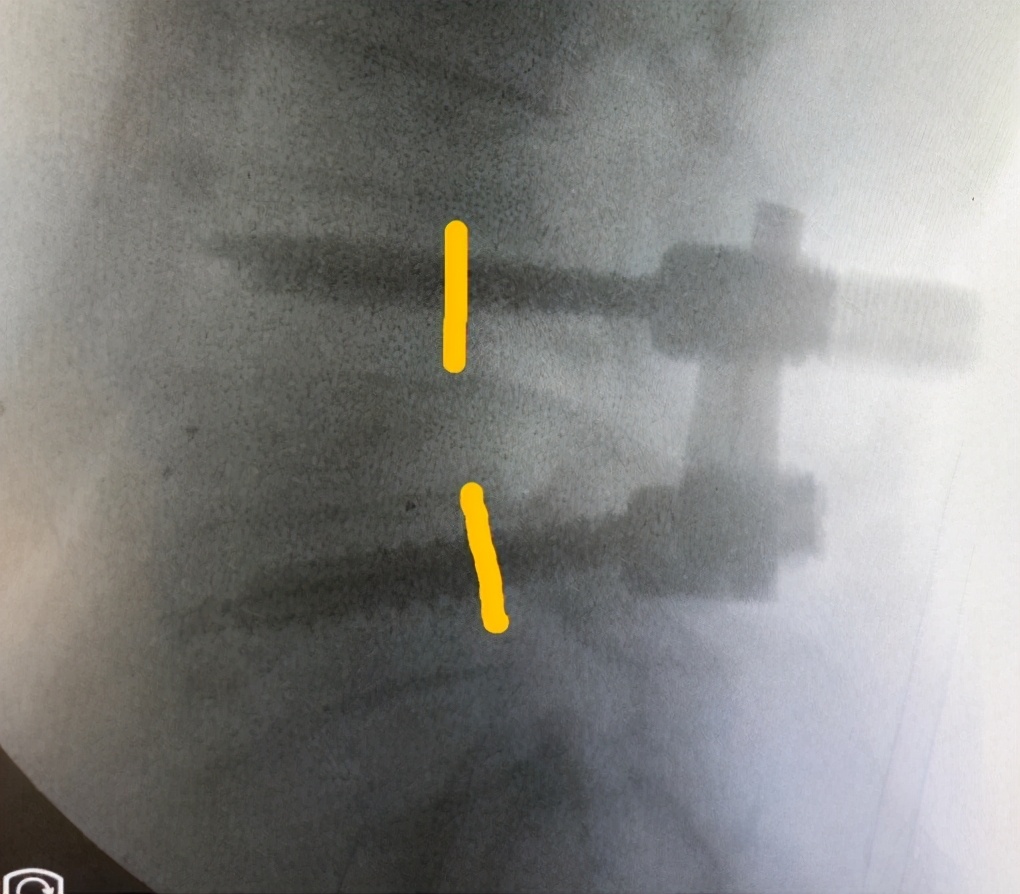

影像

诊断

1.退变性腰椎滑脱(L4-5)

2.腰椎管狭窄症

术中

术后

1.疼痛缓解

2.基本可以正常行走

VAS疼痛评分:1分;ODI残疾指数:20%